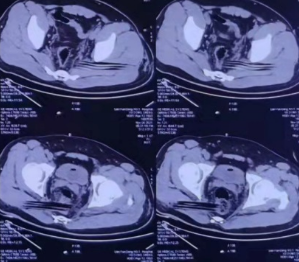

图2CT示木条异物从右侧坐骨大孔穿入、自左侧坐骨大孔穿出

图3、4CT示木条异物与直肠关系密切可能损伤直肠